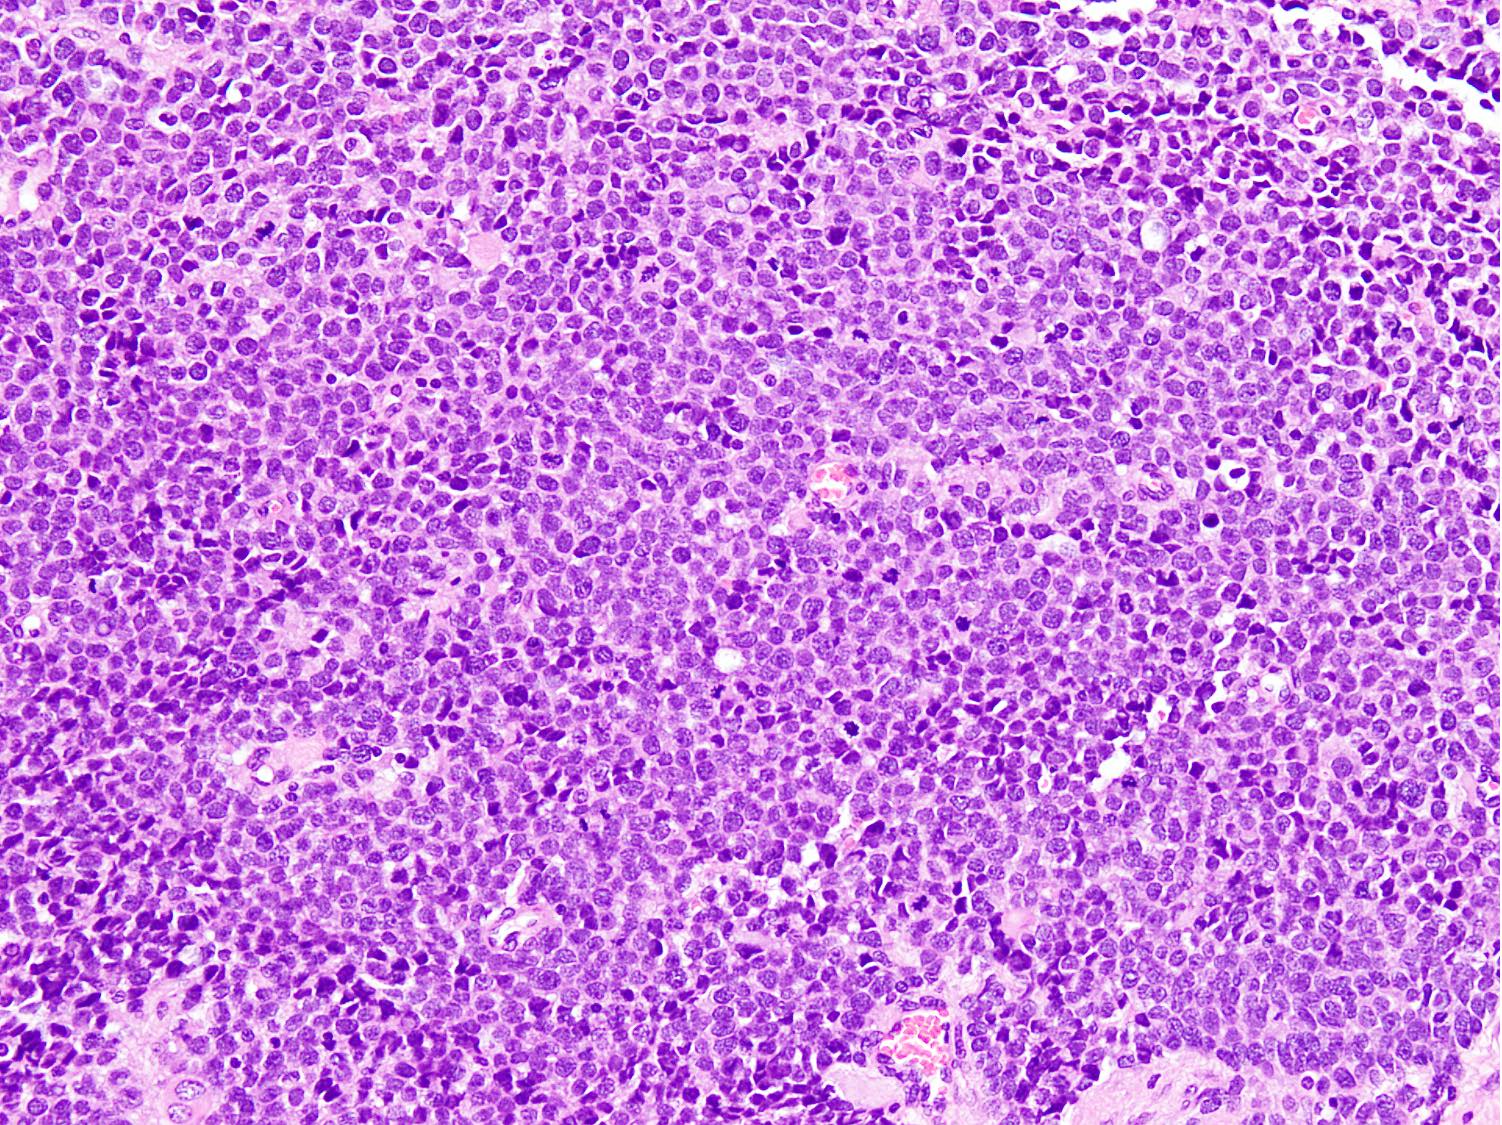

Microscopic (histologic) description

- Cellular round cell tumor

- Large clusters, nests, cords and trabeculae of primitive round cells, separated by variably thick fibrovascular septa

- Loss of cellular cohesion in the center forms alveolar-like, cystic and vague papillary appearance (Histopathology 2022;80:98)

- Layer of cells adheres to the periphery of the spaces and fibrous septa

- Small to intermediate sized monomorphic cells with scant cytoplasm

- Hyperchromatic nuclei with variable conspicuous small nucleoli

- Solid variant:

- Sheets of neoplastic cells

- Lack fibrovascular septa, pseudoalveolar spaces and dyscohesion (Cancer Genet Cytogenet 2005;163:138)

- May show rhabdomyoblastic differentiation

- Abundant mitotic activity

Microscopic (histologic) images

Contributed by Nasir Ud Din, M.B.B.S.